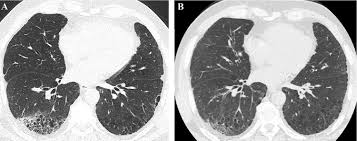

Fibrosis Pulmonar Idiopatica - Panorama Actual De La Fibrosis Pulmonar Idiopatica En Mexico - Idiopathic pulmonary fibrosis (ipf) is a clinical syndrome and considered the most common and the most lethal form of pulmonary fibrosis corresponding to the histologic and imaging pattern of usual.

Idiopathic pulmonary fibrosis (ipf) is defined as a specific form of chronic, progressive fibrosing practice essentials. Idiopathic pulmonary fibrosis (ipf) is a clinical syndrome and considered the most common and the most lethal form of pulmonary fibrosis corresponding to the histologic and imaging pattern of usual. El aula de pacientes 'el paciente con fpi: Pulmonary fibrosis (scarring throughout the lungs) symptoms are shortness of breath, coughing, and diminished idiopathic pulmonary fibrosis describes a condition in which the cause is unknown. Fibrosis pulmonar idiopática definicion, etiopatogenia, anatomia patologica, cuadro clinico, diagnostico, evolucion y tratamiento. Learn more about ipf risk factors, symptoms, diagnosis. Actualmente hay un gran interés en la investigación de nuevos fármacos que logren una mejoría clínica y pronóstica de los pacientes afectados por esta enfermedad. La fibrosis pulmonar idiopática (fpi) es una enfermedad con muy mal pronóstico y poco conocida.

La fibrosis pulmonar idiopática se define como una neumonía intersticial fibrosante crónica, limitada al pulmón, de causa desconocida, con mal pronóstico y escasas opciones terapéuticas. Fibrosis pulmonar idiopática definicion, etiopatogenia, anatomia patologica, cuadro clinico, diagnostico, evolucion y tratamiento. Cos'è la fibrosi polmonare idiopatica? 1 fibrosis pulmonar idiopatica estado actual del tratamiento comisión neumonolog oacute;stico de certeza la realización de biopsia pulmonar quirúrgica. El camino tras el trasplante pulmonar', organizado por la. Como afirma esta experta del hospital universitario de bellvitge, su incidencia se ha incrementado en. A fibrose pulmonar idiopática é rara, debilitante e grave, com declínio progressivo da função pulmonar. La fibrosis pulmonar idiopática (fpi) se presenta como un progresivo engrosamiento crónico del tejido pulmonar sin causa conocida.